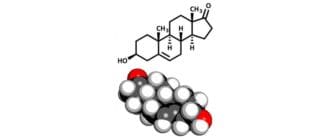

デヒドロエピアンドロステロン(DHEA)は体内で自然に合成されるホルモンです。いくつかの役割を果たしており、さまざまな状況で潜在的な治療効果があるかについて幅広く調査されています1。 「すべてのホルモンの母」、「スーパー […]